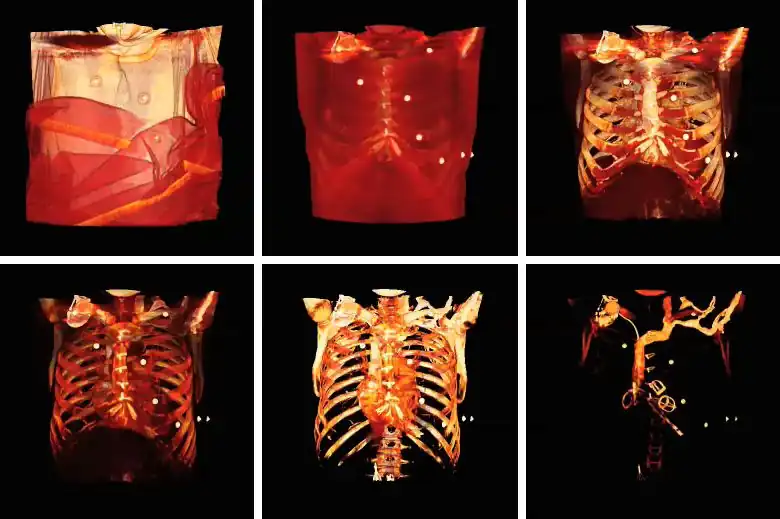

Note that the volume rendering can be contrast enhanced so as to threshold, for instance, through the voxel values to eliminate low attenuating surfaces, as illustrated in the following figure:

3D VR contrast enhancement progressively applied, from top left to bottom right panels, through the voxel value range.

Note also that the colour look-up table (CLUT) can be varied to highlight features of particular interest, as shown in the set of images below:

3D volume renderings using four different CLUTs.

The influence of the opacity table is illustrated in the following example images:

3D volume renderings using four different opacity tables.

The influence on volume rendering of various shading settings is shown below:

3D VR shading comparison.

The shading settings used for the above images are as follows:

Image Ambient Coefficient Diffuse Coefficient Specular Coefficient Specular Power

Top Left

0.15

0.9

0.3

15.0

Top Middle

0.75

Top Right

0.1

Bottom Left

1.2

Bottom Middle

1.0

Bottom Right

0.6